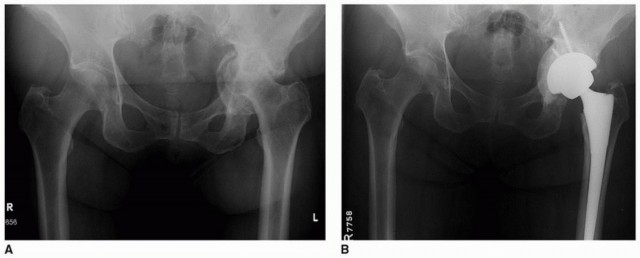

تثبيت مفصل الورك بدون أسمنت هو تقنية حديثة لاستبدال مفصل الورك تعتمد على الاندماج العظمي المباشر، مما يوفر ثباتًا طويل الأمد. يقدم الأستاذ الدكتور محمد هطيف في صنعاء هذه الجراحة المتطورة بدقة متناهية، لضمان تعافٍ سريع ونتائج ممتازة للمرضى الذين يعانون من آلام الورك المزمنة.

لطالما كانت جراحة استبدال مفصل الورك الكلي (Total Hip Arthroplasty - THA) حلاً فعالاً لتخفيف الألم واستعادة وظيفة المفصل لدى ملايين المرضى حول العالم. ومع التطور المستمر في التقنيات الطبية، ظهرت طريقة التثبيت بدون أسمنت كخيار مفضل بشكل متزايد، خاصة في أمريكا الشمالية والعديد من المراكز الطبية الرائدة.

تعتمد هذه التقنية على تصميم مكونات الحُق (Acetabular Component) بطريقة تسمح للعظم الطبيعي بالنمو والاندماج مباشرة مع سطح الغرسة، وهي عملية تُعرف بالاندماج العظمي (Osseointegration). هذا الاندماج البيولوجي يوفر تثبيتًا قويًا ومستقرًا يدوم لسنوات طويلة، ويقلل من الحاجة إلى مراجعات جراحية مستقبلية بسبب تراخي المكونات.